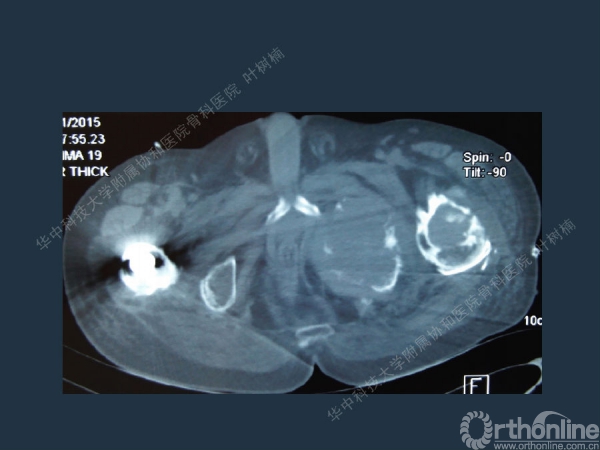

股骨侧翻修

髋臼缺损的处理